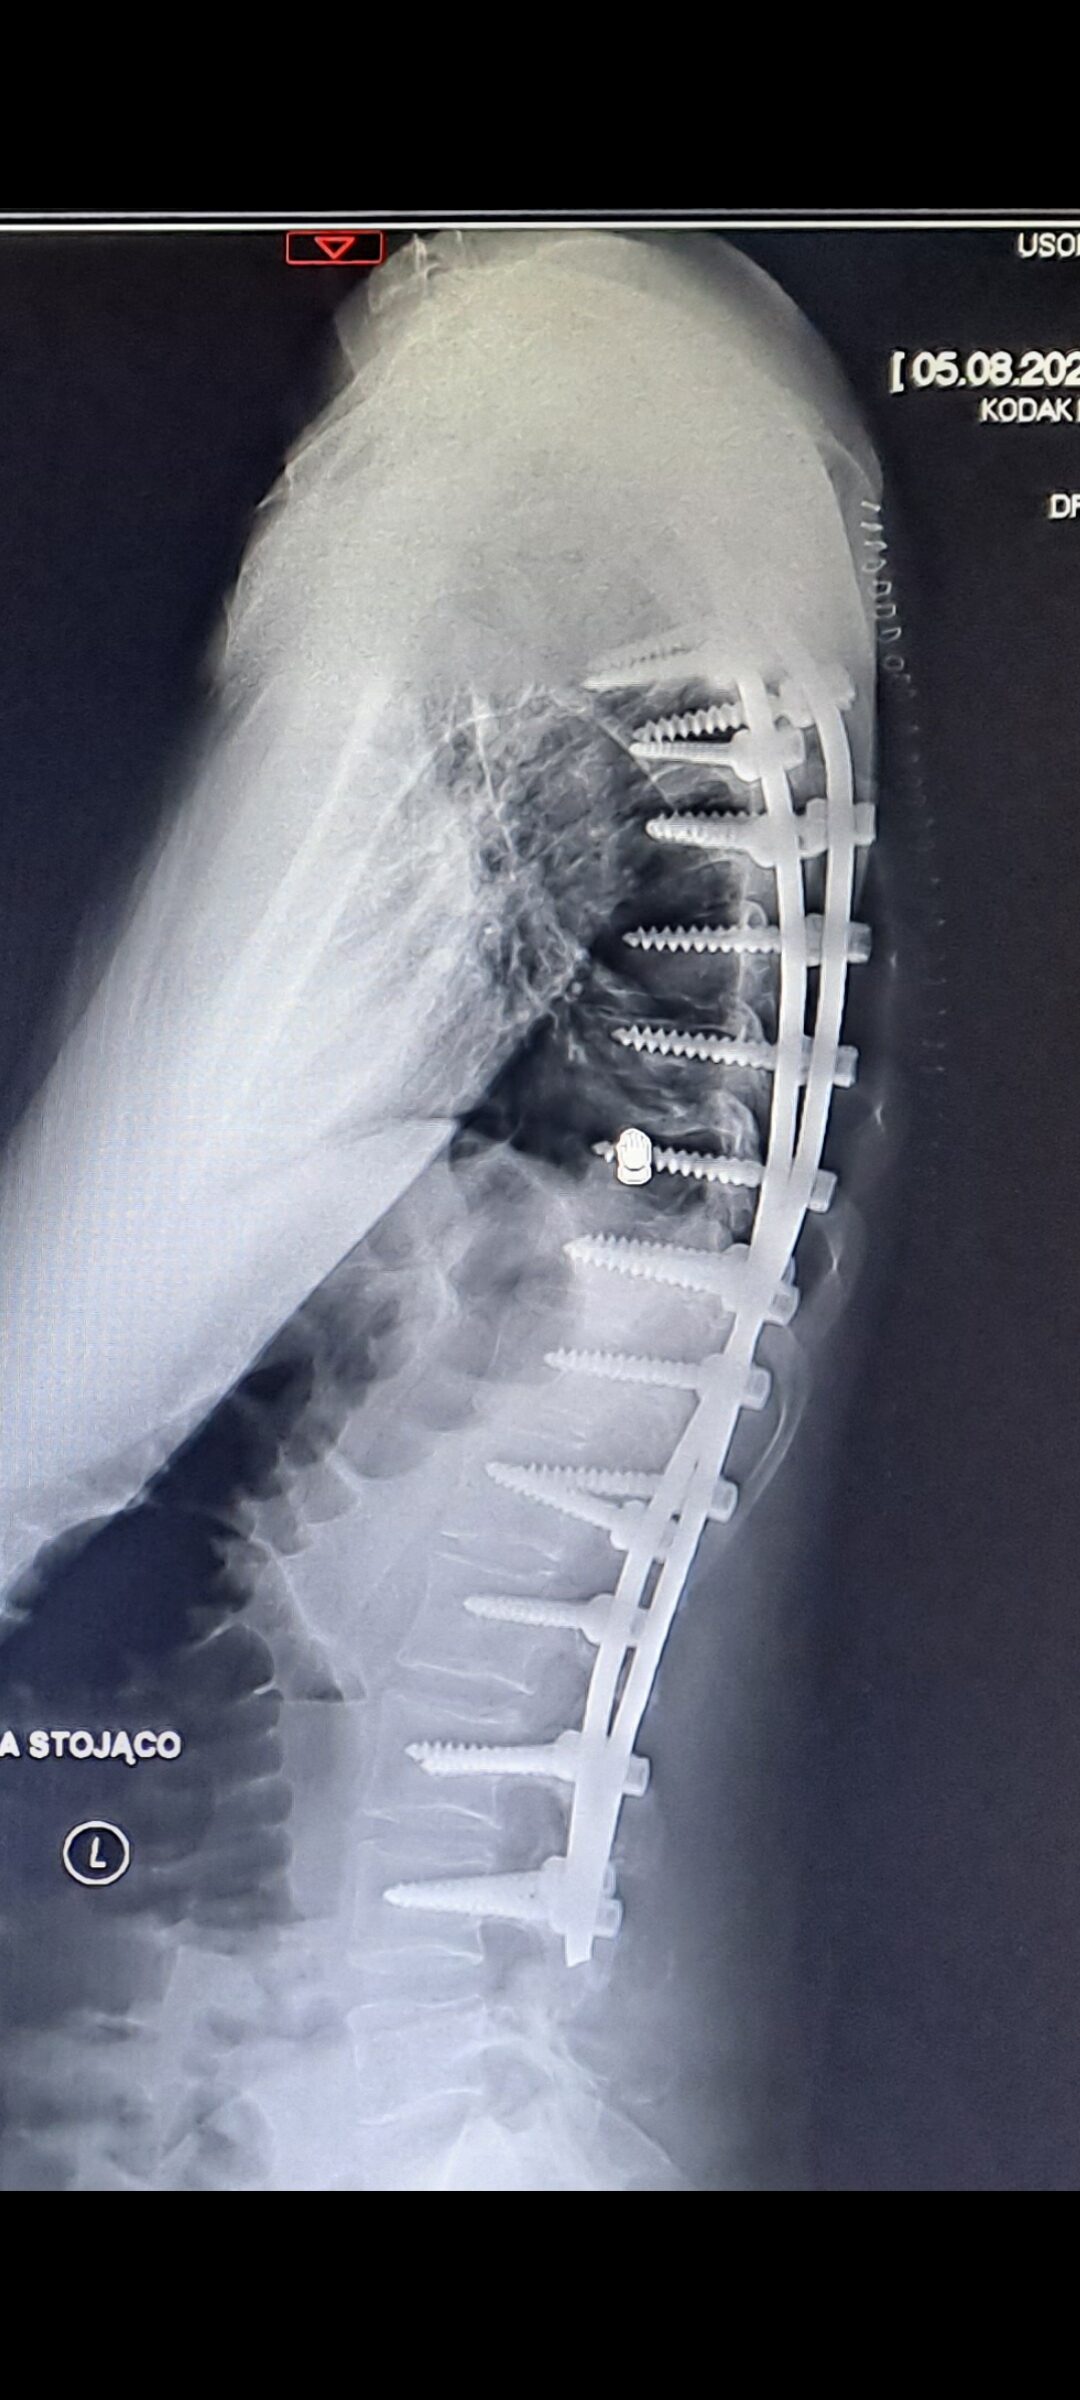

Nazywam się Emilia, mam 35 lat i od dzieciństwa zmagam się z ciężką skoliozą, przepukliną lędźwiową, guzkami Schmorla oraz osteofitozą krawędziową. Przeszłam wiele operacji i rehabilitacji, ale moja walka o życie bez bólu wciąż trwa. W 2024 roku przeszłam cztery kolejne operacje kręgosłupa. Podjęłam decyzję o wszczepieniu neurostymulatora rdzenia kręgowego, który miał pomóc mi funkcjonować bez bólu. Niestety, podczas operacji doszło do śródoperacyjnego zakażenia bakterią pałeczka ropy błękitnej, co zapoczątkowało dramatyczną walkę z infekcją. Zastosowano ciężką antybiotykoterapię, jednak konieczne było usunięcie neurostymulatora i kilkukrotne czyszczenie kręgosłupa. W tym czasie byłam hospitalizowana w szpitalu MSWiA oraz na oddziale Neurozakażeń Szpitala Zakaźnego w Warszawie. Każdego dnia przechodziłam zabiegi w komorze hiperbarycznej oraz odciąganie płynów z kręgosłupa.

Choć zrobiłam wszystko, by wrócić do sprawności, komplikacje po operacji doprowadziły do obluzowania się śrub stabilizujących, które teraz muszą zostać pilnie wymienione. Stabilizacja była wykonywana komercyjnie, dlatego istnieje duże prawdopodobieństwo, że również za kolejną operację będę musiała zapłacić samodzielnie. Jestem samotną mamą 12-letniego syna i każdego dnia staram się być silna dla niego, mimo niewyobrażalnego bólu.